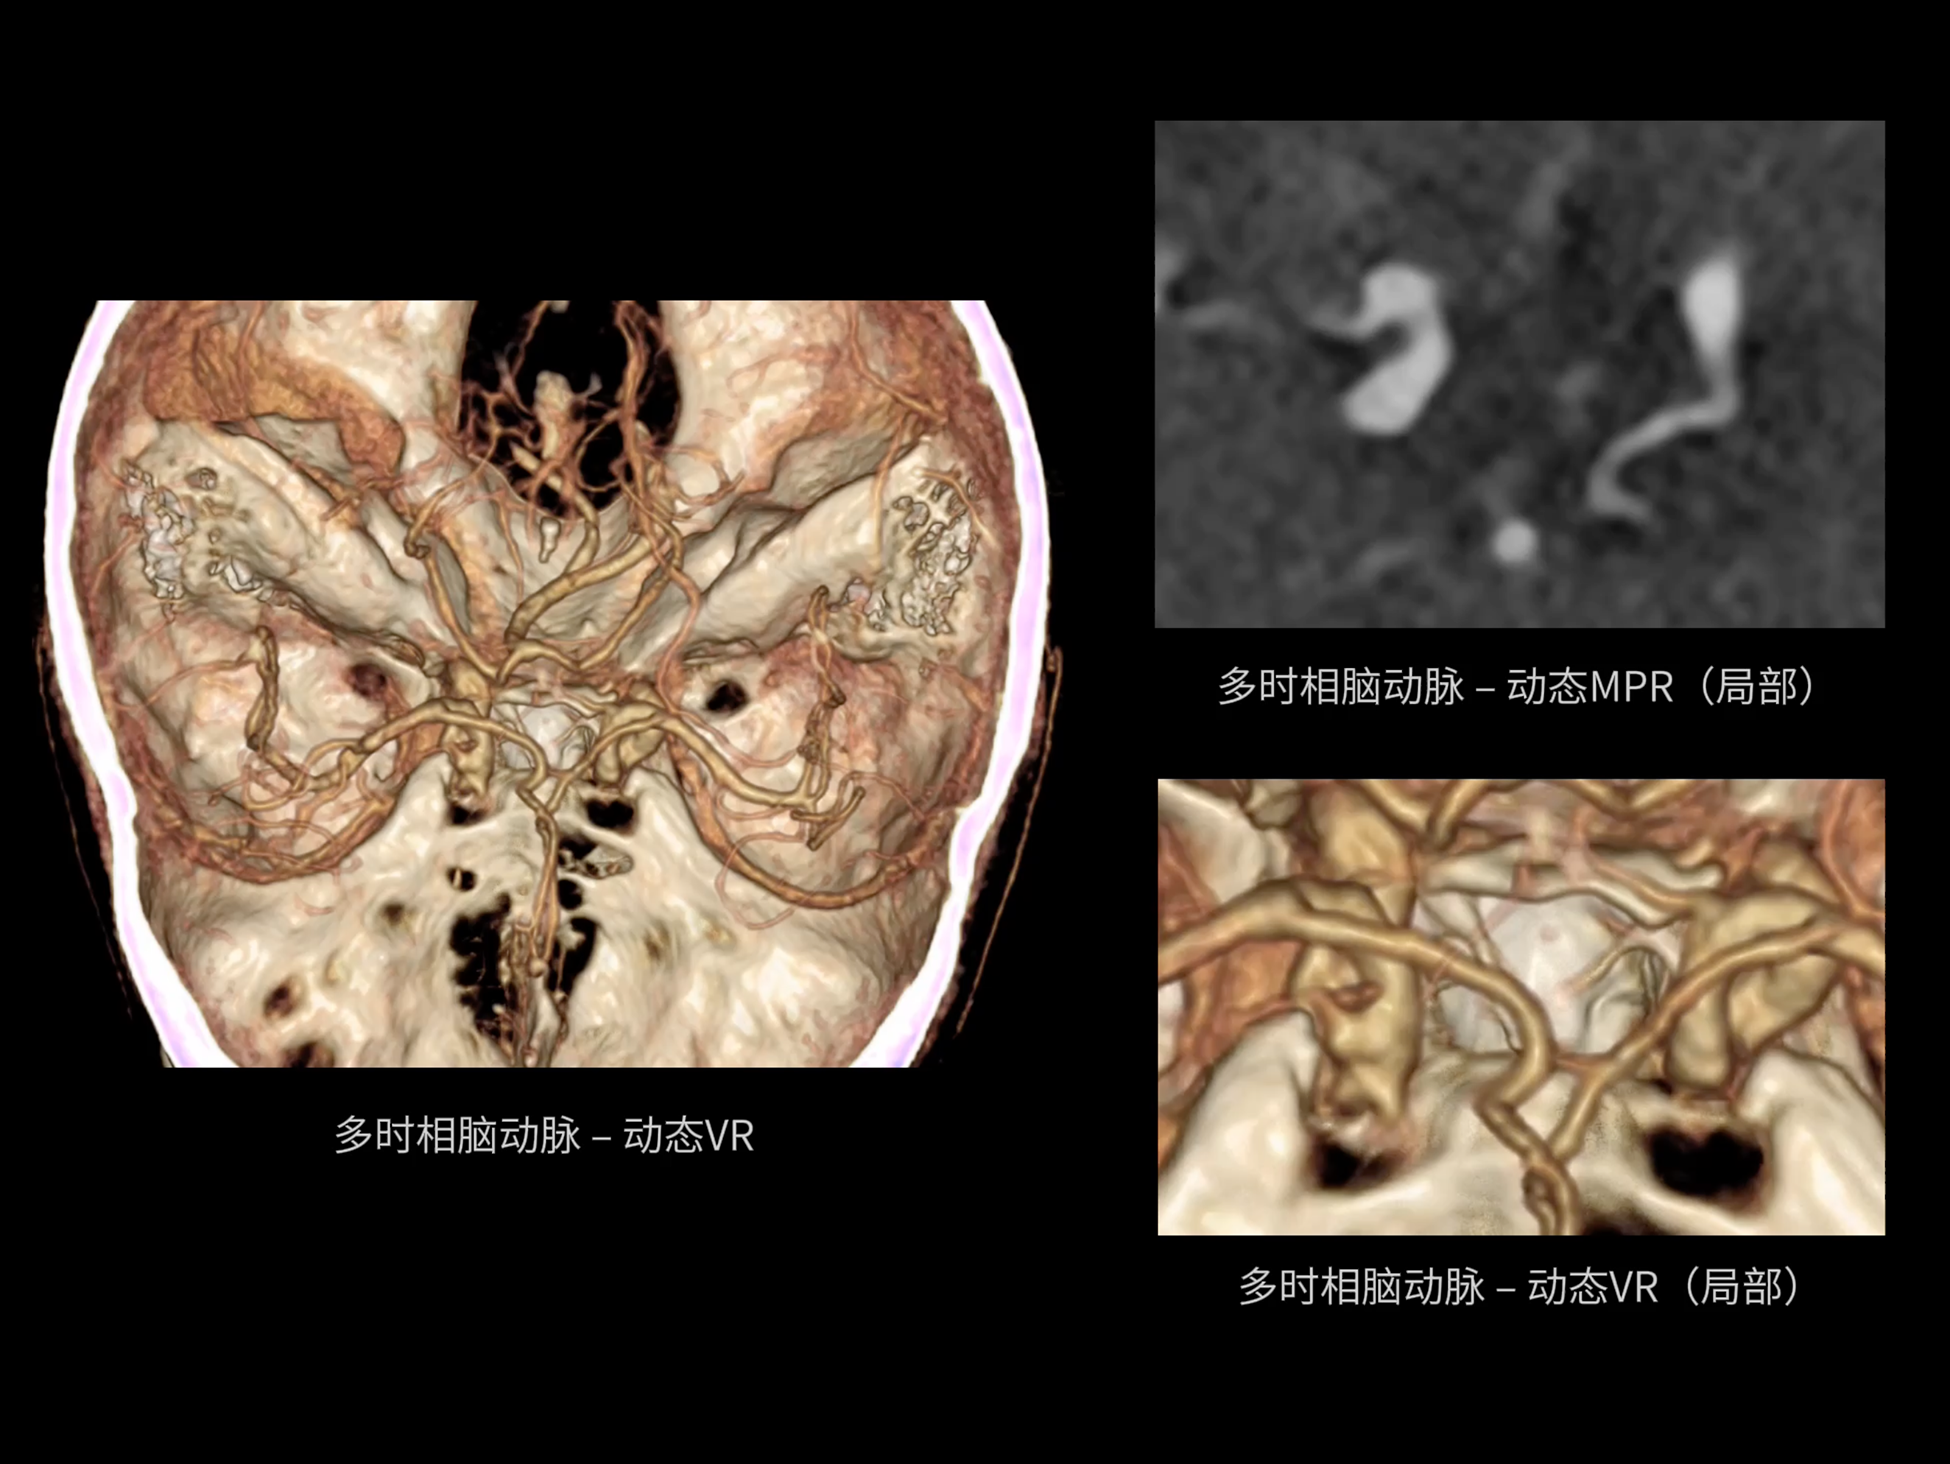

全身各部位动态CT成像

uCT SiriuX® 以全新双宽体系统架构,同步实现超高时间分辨率与宽体容积覆盖兼得,全面释放性能潜能,敏锐捕捉人体生理运动全景,带来动态影像新视角。

巅峰系统形态

双宽体“零”噪声时空探测器,Z 方向覆盖达16 cm,单圈即可完整扫描头颅、心脏等关键器官,结合超高时间分辨率,可实现真正意义上的全身各部位高清动态成像,让每一次扫描都更高效、更精准。

uCT SiriuX® 以16cm超宽Z轴覆盖,使超高时间分辨率应用于完整器官成像。无论是心脏搏动还是关节运动,整个目标区域可在同一瞬时被完整、清晰地捕捉,彻底消除时序误差,实现从“局部瞬间”到“全器官瞬时”的成像跨越。